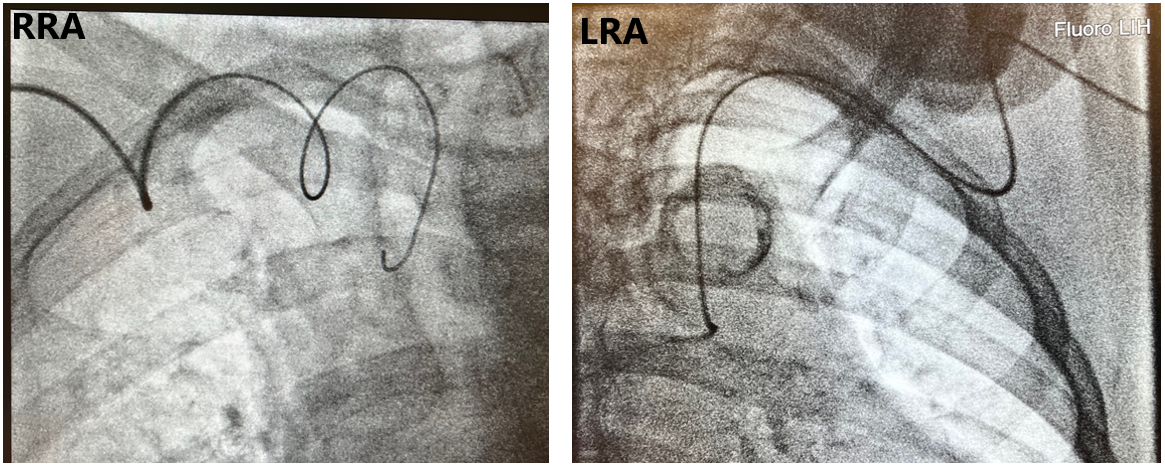

There are 3 important factors when considering subclavian tortuosity in terms of how it may impact ORE. First is the degree of tortuosity. Mild tortuosity may not have an impact on ORE, especially for experienced “radial-first” operators. However, as tortuosity becomes more pronounced, this can pose a problem for selective coronary engagement and guide support. As catheters move across the trachea fluoroscopically, the difficulty of catheter manipulation increases. Subclavian loops or an “elephant’s head” tortuosity can pose technical challenges for operators (Figure 4). Research suggests that, for catheters passing the spine greater than 1 cm on fluoroscopy, exchanging for Judkins catheters from universal radial approach catheters may provide faster coronary engagement.16 As the severity of tortuosity increases, this can add fluoroscopic time as well as ORE if strategic shield placement is not attended to by operators.